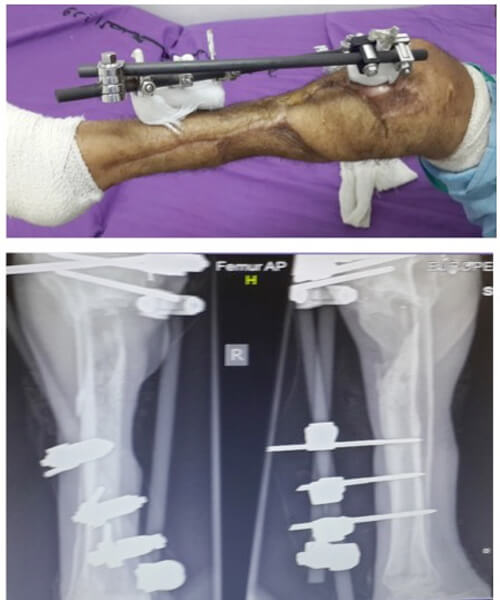

A 20-year-old man presented 46 days after a GSW injury to his right leg. He sustained a Gustilo IIIc fracture of the proximal tibia and fibula with division of the popliteal artery (Figures 13 & 14). The vascular defect was bridged acutely with a vein graft by a vascular surgeon. All toes were necrotic from either acute ischaemia or embolic injury. All compartments below the knee had been affected during the acute ischaemic episode. There was no neural function below the knee: the patient had an insensate foot with a pressure sore on the heel. This equated to a poor foot on an ‘almost dead’ stick.

Figure 13: Right lower leg following compound fracture and vascular injury. The sponge of a vacuum

assisted closure system is still in situ. Extension of the medial wound for access during

acute vascular repair as well as to allow extension as a medial fasciotomy.

Figure 14: Bone loss in the proximal tibial metaphysis.

The patient had been immobile for 1.5 months, he was thin and unwell but not septic yet. He had received 22 ‘debridements’ of this limb with necrotic tissue being removed from the deep and superficial posterior compartments. A vacuum dressing was in situ.

It was explained to the family and patient that the prognosis for this leg was very poor; both for function and chances of bone union. The risk of future infection and sepsis from retaining this leg was emphasised. Despite four family meetings, the young man refused amputation.

He was taken to theatre for examination under anaesthetic (EUA) and further debridement. Pus was present in the bone medullary cavity when the vacuum dressing was removed (Figure 15). The only flap option was a medial adhoc perforator flap based on a perforator proximal to the zone of arterial repair.

Compete debridement was undertaken to eradicate septic foci. Once clean, a Masquelet type procedure and closure with the medial adhoc perforator flap was undertaken providing limb salvage (Figure 16).

Figure 16: Flap cover following thorough bone debridement and Maquelet cement plug.

Split skin graft covers the flap donor site and any remaining soft tissue defects.

The patient was discharged home 10 days later with no new signs of infection and all areas closed by flap and SSG. At three months review, he was mobile on one leg with crutches. He was well and grateful to have the time to consider his options; he could accept the functional limitations of the leg. He was considering elective amputation if he could be guaranteed a good prosthesis. One year from surgery (Figure 17), he still retains the functionless leg with no episodes of clinical osteomyelitis but minimal chances of bone union. He will have to come to his decision shortly.